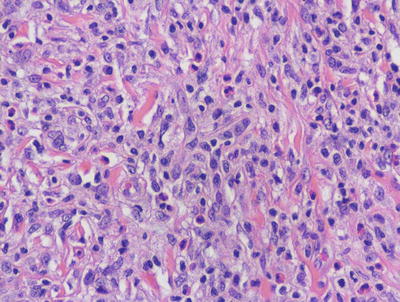

In LCH, the epidermis demonstrates focal parakeratosis overlying varying degrees of spongiosis that is diffuse throughout the epidermis. In most cases, there is abundant exocytosis of Langerhans cells into the epidermis (Fig. 22.3). Langerhans cells can usually be identified based upon cytologic features that include reniform-shaped, grooved, or folded nuclei and abundant cytoplasm (Figs. 22.4 and 22.5). Anti-CD1 a immunohistochemistry is useful in cases when the nature of the infiltrating cells is not readily apparent. Intraepidermal eosinophils are also quite common. Cytologic atypia and significant mitotic activity are rarely encountered. Some cases fail to demonstrate exocytosis of Langerhans cells into the dermis. Treatment with topical corticosteroids prior to biopsy may also suppress exocytosis and mask the diagnostic features.

Fig. 22.3

Marked epidermotropism of Langerhans cells into the epidermis is seen in most cases of Langerhans cell histiocytosis

Fig. 22.4

Langerhans cell histiocytosis is comprised of sheets of Langerhans cells with grooved or reniform nuclei and ample eosinophilic cytoplasm. Eosinophils are usually present throughout the infiltrate